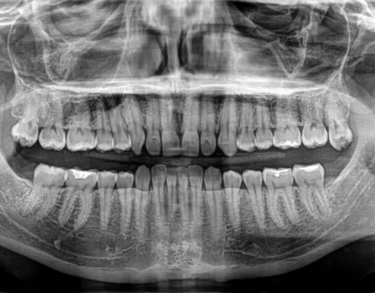

Zdjęcie pantomograficzne, znane również jako RTG panoramiczne, to jedno z najczęściej wykonywanych badań stomatologicznych. Umożliwia uzyskanie pełnego obrazu wszystkich zębów, kości szczęki i żuchwy oraz stawów skroniowo-żuchwowych w jednym ujęciu.

W naszej pracowni RTG stomatologicznego w Gdyni wykonujemy zdjęcia panoramiczne, które stanowią podstawę diagnostyki przed rozpoczęciem leczenia zachowawczego, chirurgicznego czy ortodontycznego. Badanie pozwala ocenić ogólny stan uzębienia, wykryć próchnicę, stany zapalne, torbiele czy inne nieprawidłowości w obrębie jamy ustnej.